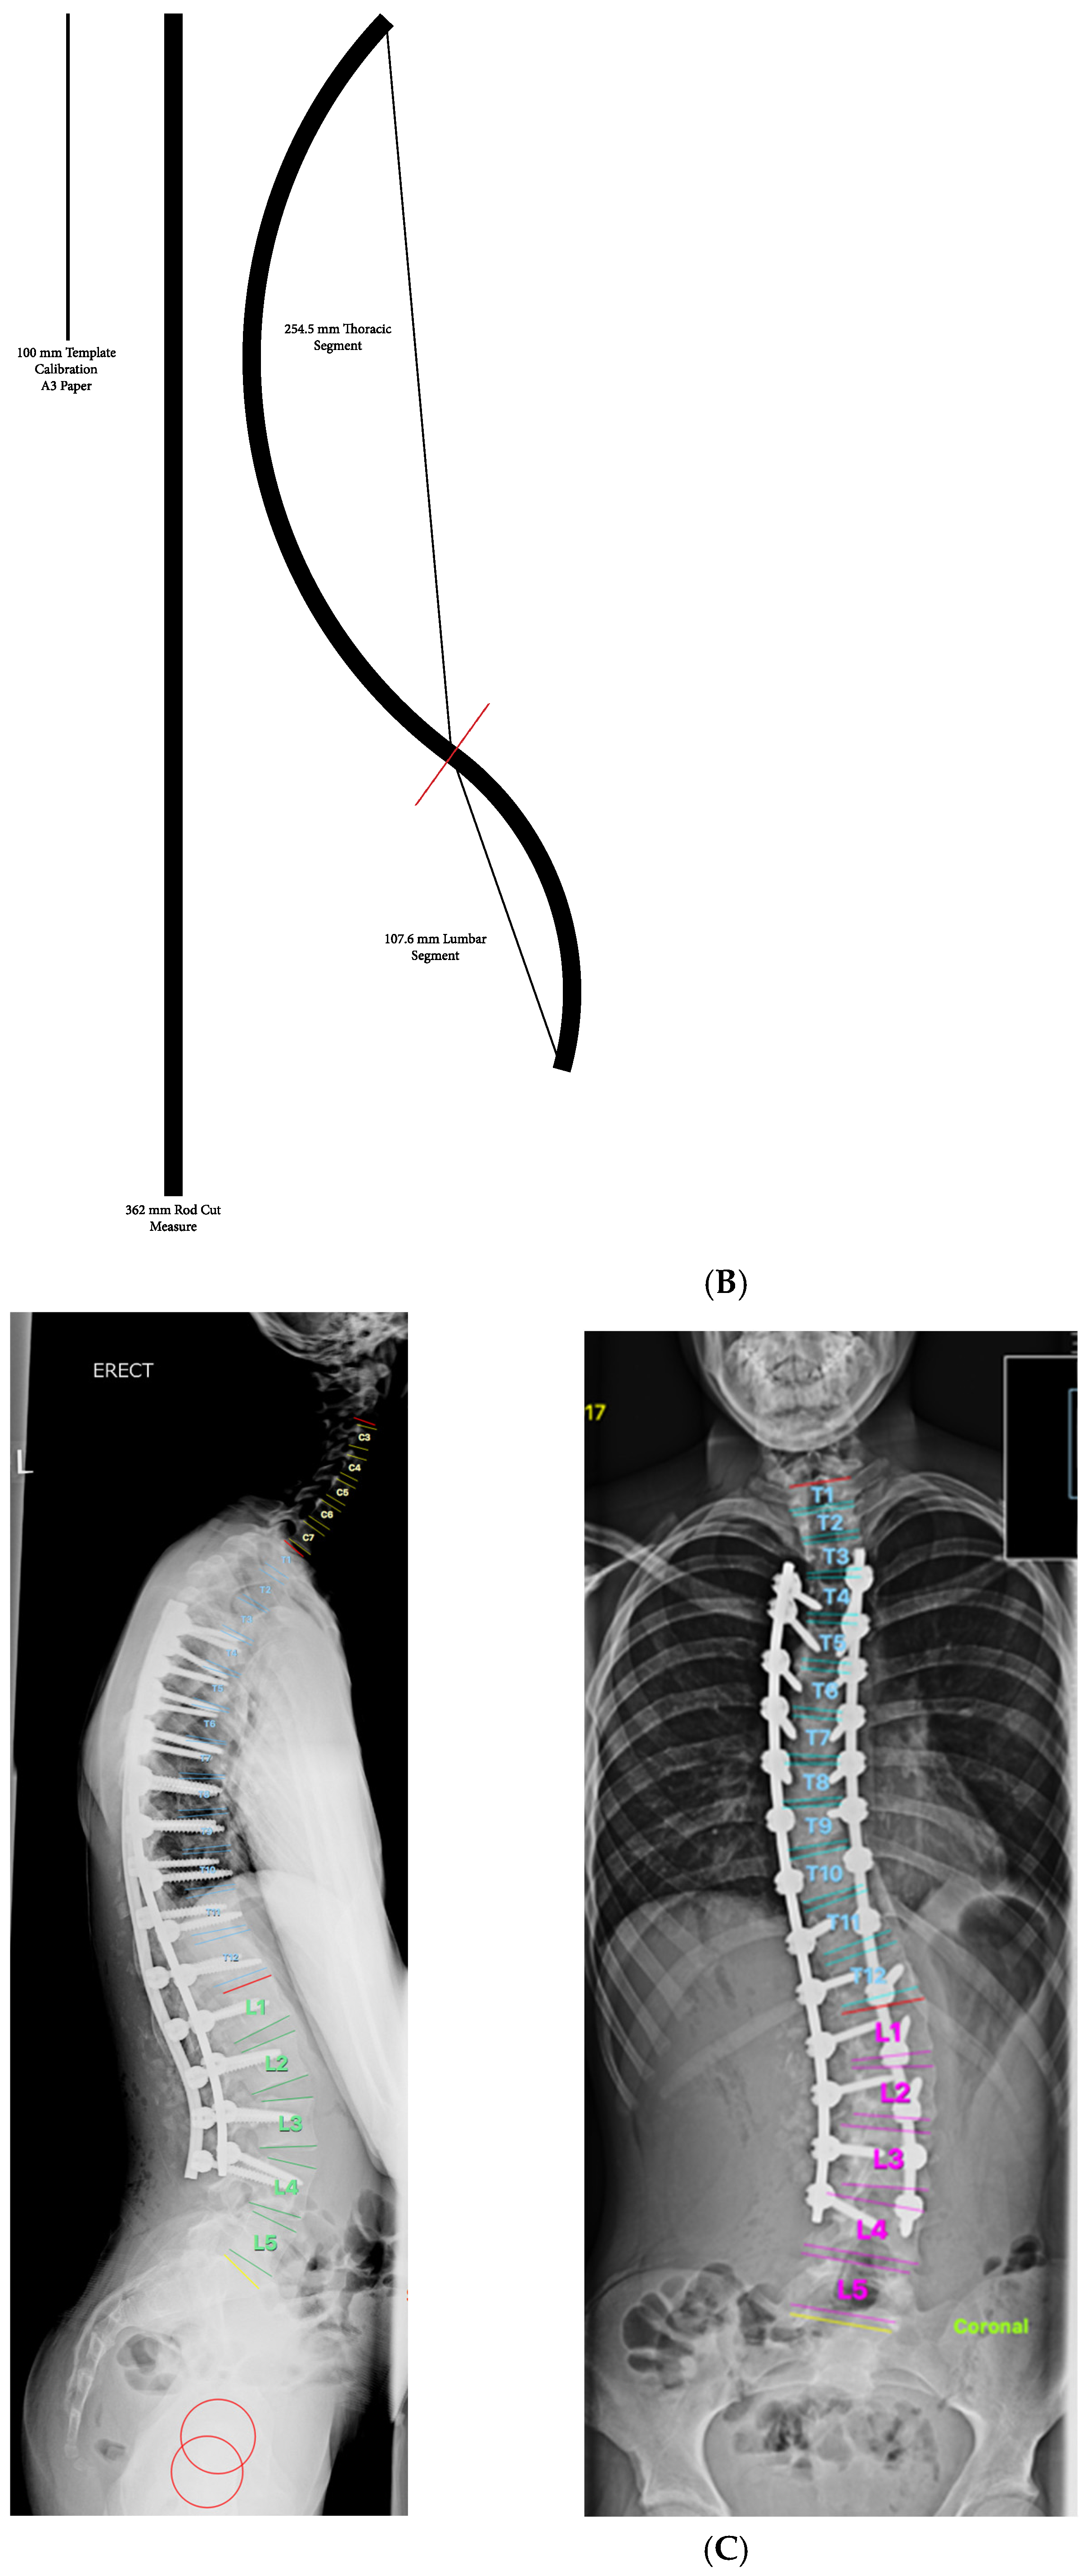

2. Materials and Methods

- Restoring TK to a value of 20–40° regardless of pre-operative TK value.

- Post-operative TK achieved was within 5.5° of the value predicted using templating.

- Excellent coronal plane correction in addition to the correction of TK.